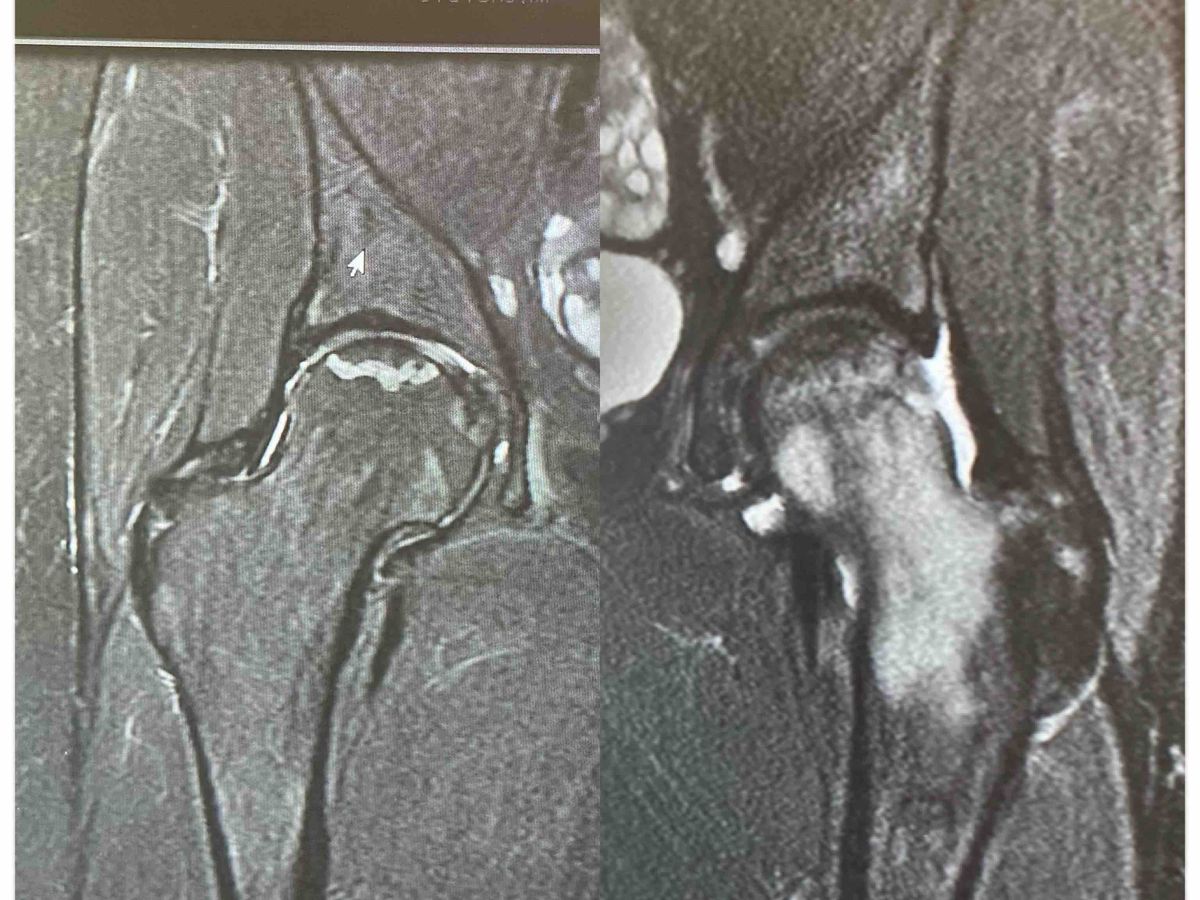

Hi everyone. I’m Kaylee a 20 year old female, who is battling lots of health problems. It all started with mental health bpd, anxiety, depression, ptsd, etc. I thought this was a lot at the time… I always felt something was wrong and kept “digging” to find something..later on finding I have hypothyroidism and hashimotos. Basically my body is attacking my thyroid and doctors don’t like to get to a root cause they just like throwing you some medicine. This is why our health system is a joke.that’s a different topic though. Anyway not even 6 months later I started experiencing super bad hip pain in my right hip. I went on and on for months not thinking anything of it.(I have scoliosis so I’m always in some kind of pain) I thought maybe I just overworked something. X-rays later they found just some bone growth over my femur bone and thought maybe that was rubbing. I still felt something was wrong. 2 MRIs later and lots of blood work I got diagnosed with AVN (Avascular necrosis) finding it first in my right hip. I have a lot of fluid and inflammation. I’ve been on crutches for 4 weeks now. I tested positive for sclerderma but we are hoping it’s a false positive. If not it adds a lot more complications with a core decompression surgery. I won’t be able to walk for eight weeks and it will take 3 months to fully recover. The chances of this surgery to be successful are very slim with it being a new surgery and not knowing long-term effects. I’m scared and I’m lost and I still feel I’m a victim to all of this. I’m struggling financially with getting rid of animals not being able to afford them but have my best interest to have what’s best for them and it hurts. I hate asking for money and this took a lot of strength for me. I’m trying not to look at the world as such a bad place but it’s hard when I can’t do day to day things.not to mention my liver problems and blood work having to be done every month. Life’s hard right now and it’s hard to see the bright when everything you love gets taken away from you in a flash and your helpless. I’m doing this more so I can have my animals and give them a better life and what they deserve. Pictures and videos will be posted as updates. If you read this far I appreciate you. Here’s a video for better understanding. :